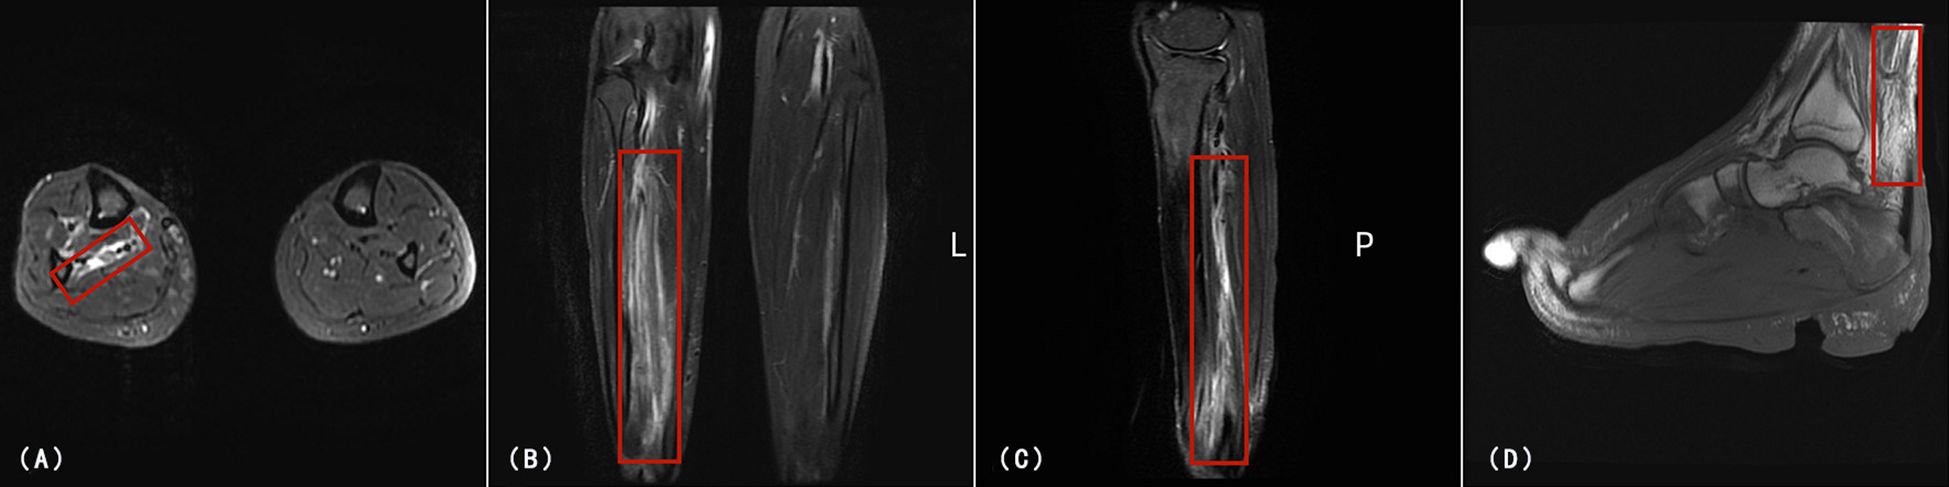

Background: Enteropathy associated T-cell lymphoma (EATL) is a rare and aggressive subtype of peripheral T-cell lymphoma, most commonly associated with celiac disease (CD). It typically presents with gastrointestinal symptoms and carries a poor prognosis. Cutaneous involvement as the initial manifestation, particularly in the form of refractory skin ulcers in young patients, is rare. Case Summary: We report a 28-year-old male who presented with a one-year history of refractory, non-healing ulcers on the right foot and several years of chronic diarrhea, initially misdiagnosed and treated as a chronic infection in April 2019. Despite multiple antibiotic regimens, surgical debridement, and immunosuppressive therapy, the lesions progressed symmetrically to involve the right hand and left thigh. The patient underwent amputation of the right lower limb and right hand in October 2020. One month later, the patient developed acute peritonitis secondary to jejunal perforation. Laparotomy revealed a transmural tumor mass, and histopathological and immunohistochemical analyses confirmed EATL (CD3+/CD103+/TIA-1+/GRANB+, CD5-/CD8-, Ki-67 ~70%). The patient died of multiorgan failure three weeks postoperatively in December 2020. Conclusion: This case underscores that EATL may manifest with widespread cutaneous ulcers more than one year before the onset of severe gastrointestinal symptoms. In patients with chronic diarrhea and refractory skin ulcers, celiac disease should be excluded, while cutaneous lesions should be recognized as potential paraneoplastic manifestations of an underlying lymphoma. Diagnostic delays—driven by anchoring bias and insufficient tissue sampling—are critical contributors to advanced disease at presentation and poor clinical outcomes.